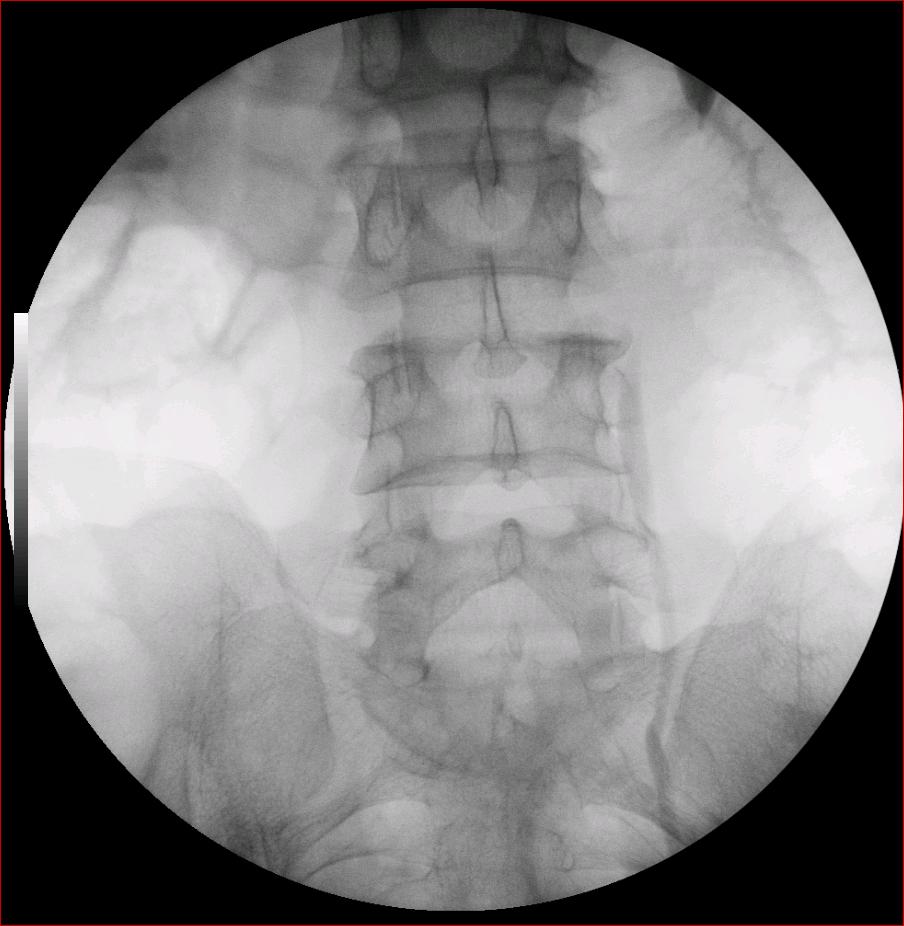

以下是引用luoxinjun在2008-2-18 15:54:00的发言:[br]右肾积水,右输尿管下端结石

以下是引用zhangxiangjun在2008-2-18 21:01:00的发言:[br]右输尿管盆段末端结石,继发其近端输尿管、右肾积水。

以下是引用hexue在2008-2-18 17:33:00的发言:[br]右输尿管下段结石并右肾及右输尿管积水扩张

以下是引用杀毒软件在2008-2-18 16:24:00的发言:[br]右输尿管下段结石,肾盂积水。